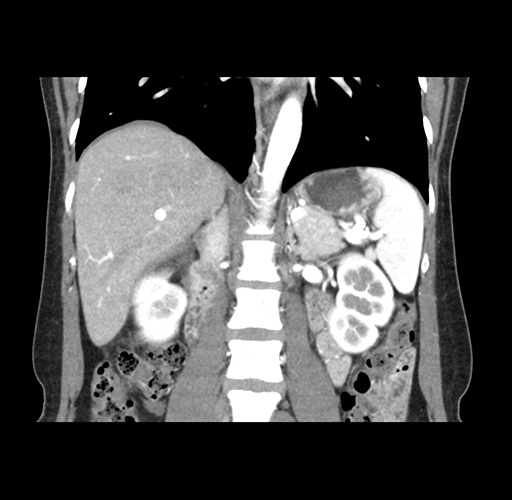

Imaging Analysis

Look through the patient's CT scan to identify any areas of concern for the necessary procedure.

Based on your CT findings, which issue(s) would give reason for "planned slowing down moment(s)" in this case?